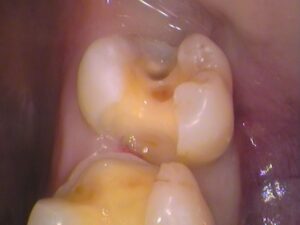

奥歯の歯の3本です。

5番目、6番目、7番目の歯があります。

よく見てみると、

青枠の箇所に「レジン」というプラスティックの合成樹脂が詰められてあります。

白い材料なので一見分かりにくいですが、経年劣化による変色もあり、継ぎはぎみたいに歯に埋められています。

レントゲン(エックス線)検査で治療前に確認済みですが、このレジンの中で虫歯があります。